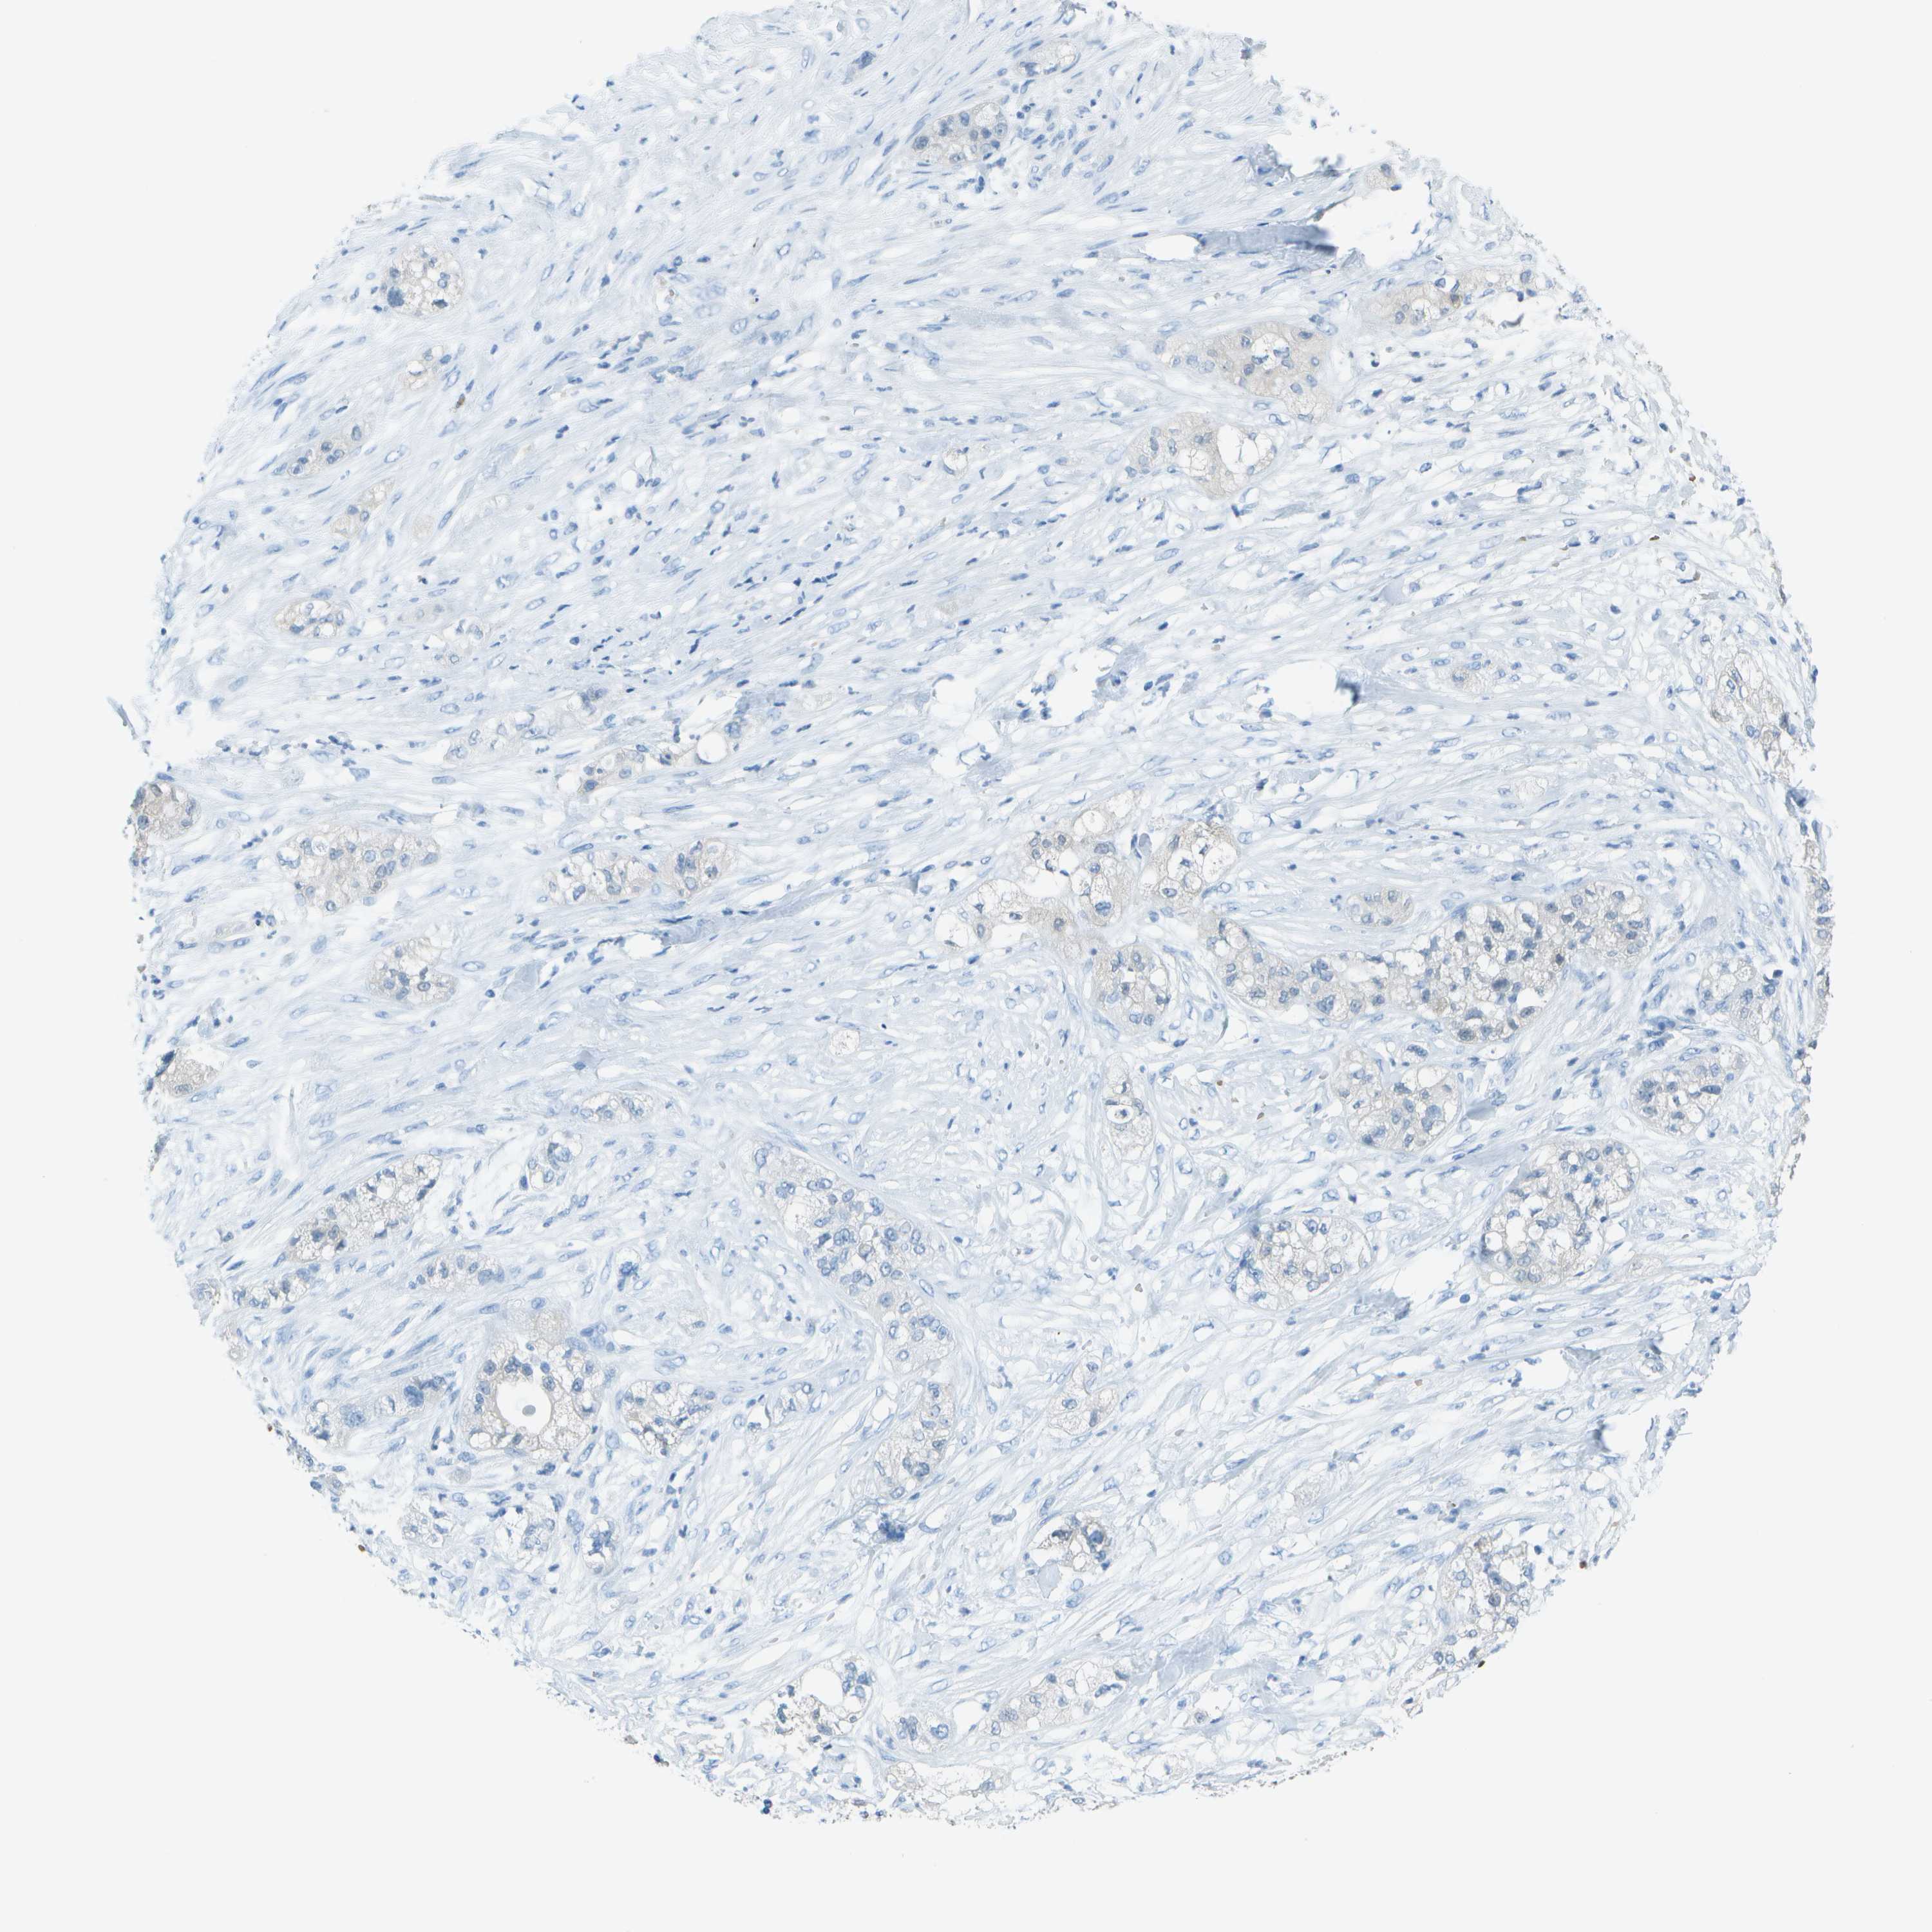

PANCREATIC CANCER - Protein expressioni

A mouse-over function shows sample information and annotation data. Click on an image to view it in a full screen mode. Samples can be filtered based on level of antibody staining by selecting one or several of the following categories: high, medium, low and not detected. The assay and annotation is described here.

Note that samples used for immunohistochemistry by the Human Protein Atlas do not correspond to samples in the TCGA dataset.

Antibody stainingi

Antibody staining in the annotated cell types in the current human tissue is reported as not detected, low, medium, or high, based on conventional immunohistochemistry profiling in selected tissues. This score is based on the combination of the staining intensity and fraction of stained cells.

Each image is clickable and will lead to virtual microscopy that enables deeper exploration of all samples and also displays staining intensity scores, fraction scores and subcellular localization as well as patient and tissue information for each sample.

Antibody CAB003696

Adenocarcinoma, NOS

Adenocarcinoma, metastatic, NOS